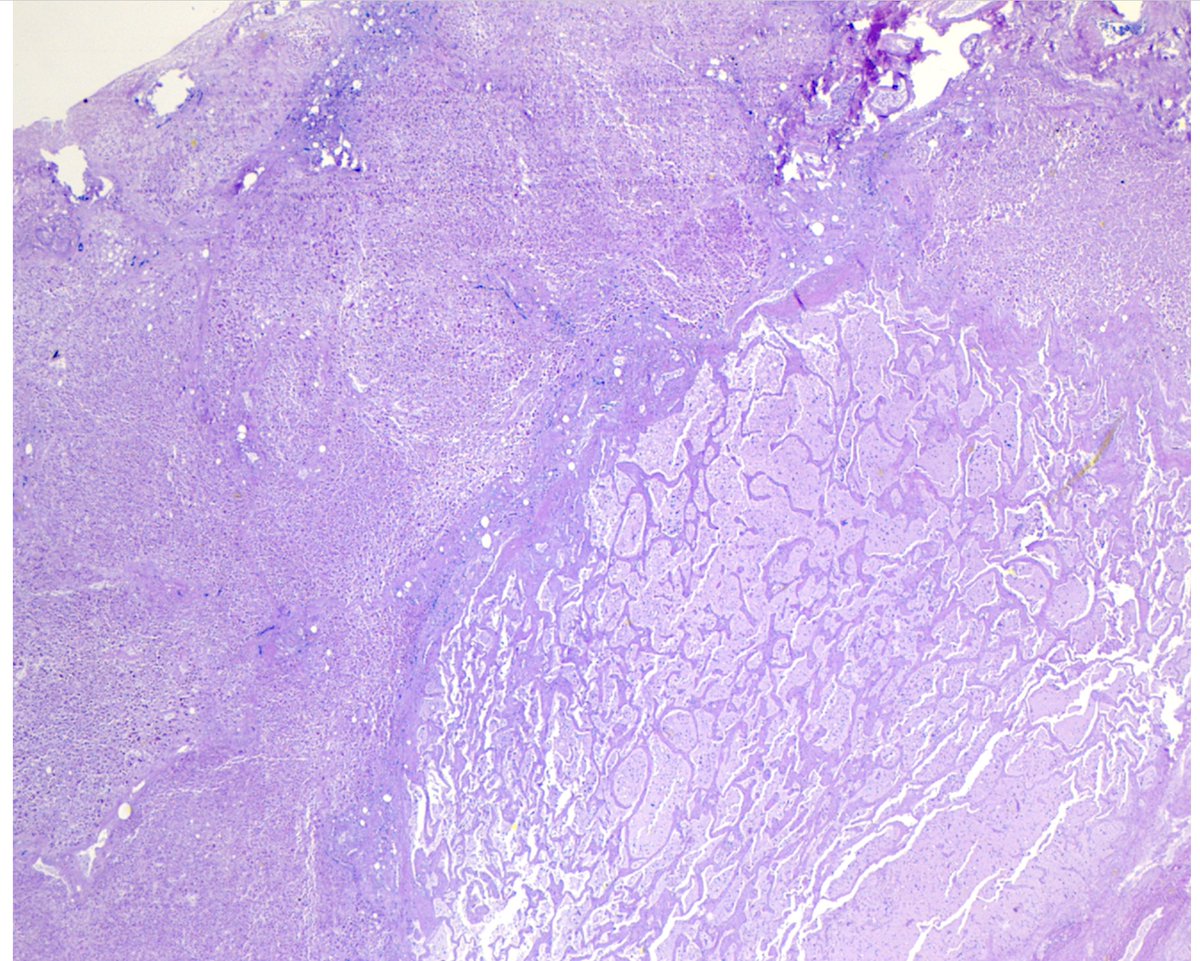

#MTPathUnknown #272

For medical students

What is the organ?

What is the general process (bottom half of image), and what features of the image help you identify the process?

My next YouTube lecture will cover this general topic